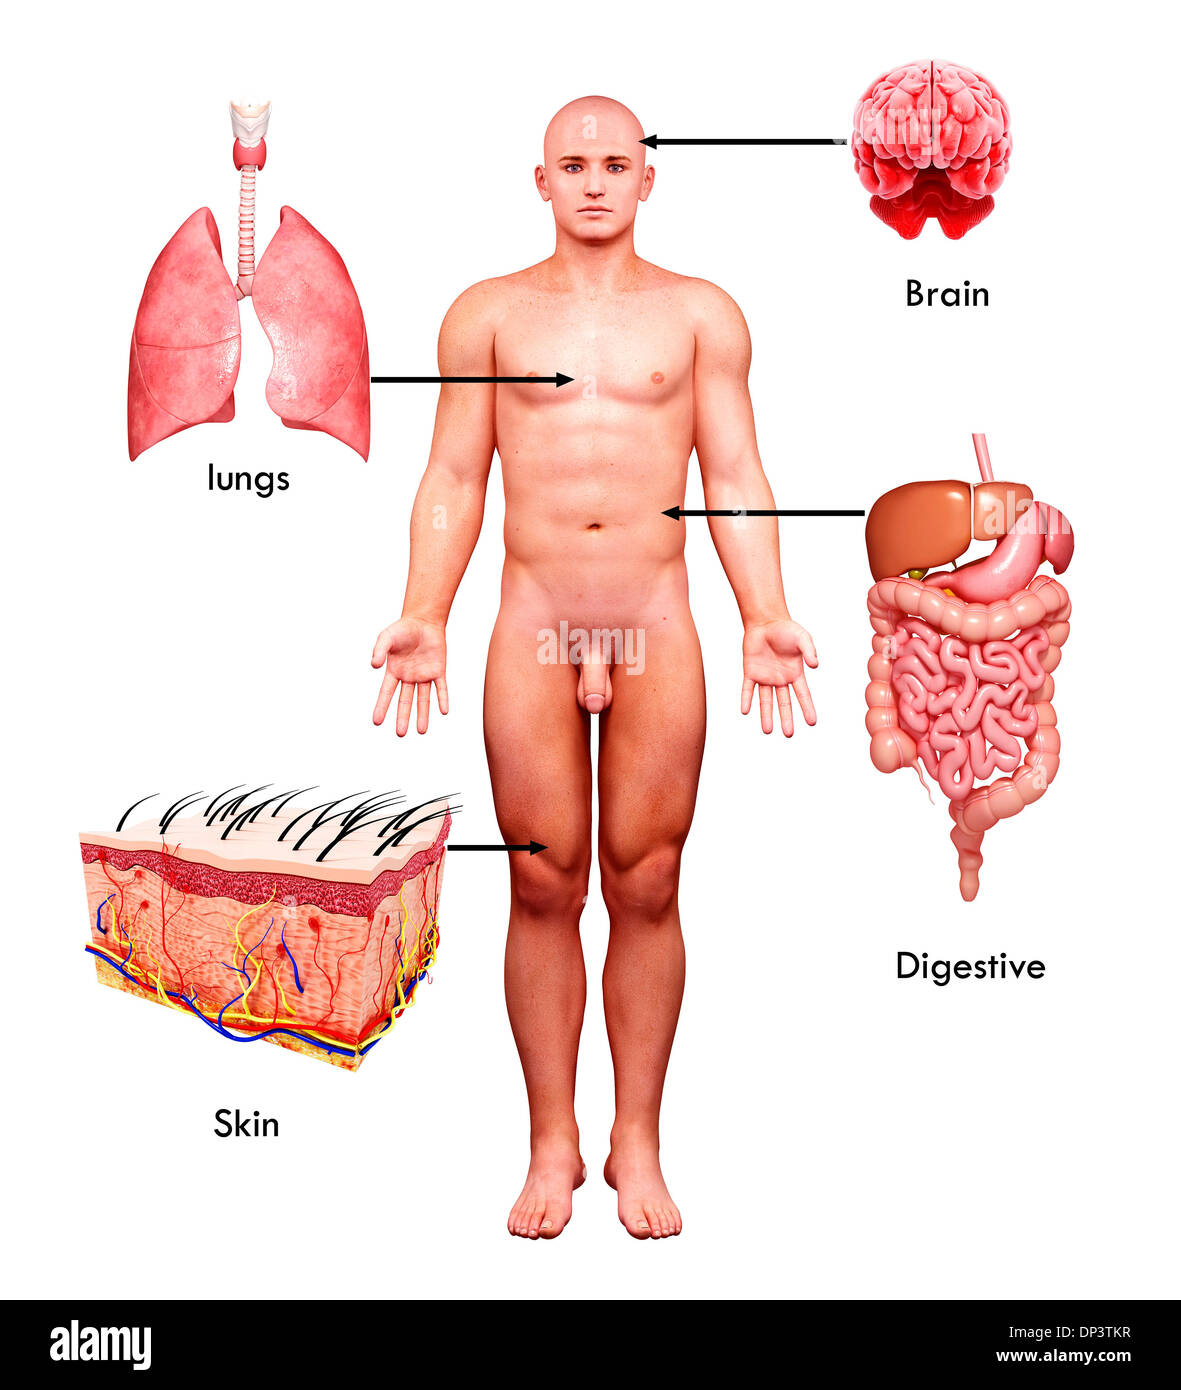

Male anatomy, artwork Banque D'Imageshttps://www.alamyimages.fr/image-license-details/?v=1https://www.alamyimages.fr/male-anatomy-artwork-image65238763.html

Male anatomy, artwork Banque D'Imageshttps://www.alamyimages.fr/image-license-details/?v=1https://www.alamyimages.fr/male-anatomy-artwork-image65238763.htmlRFDP3TKR–Male anatomy, artwork